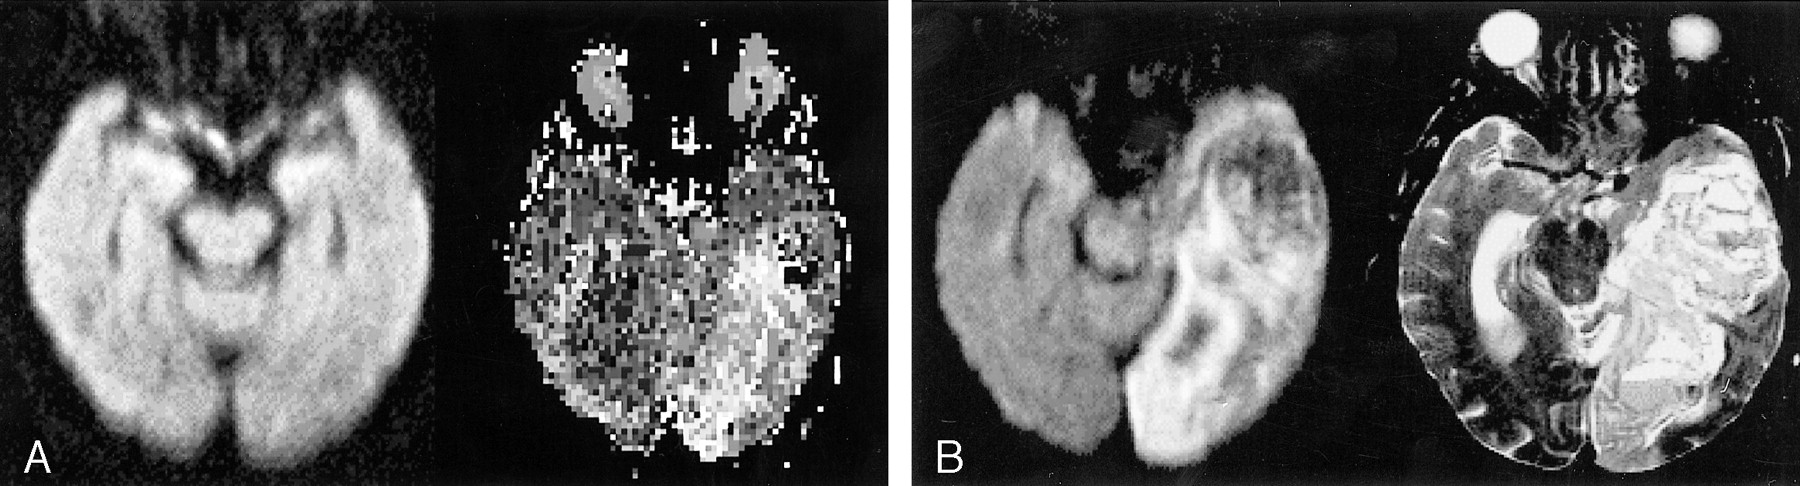

For seven of the 16 patients, diffusion imaging findings were entirely normal (Fig 1A). For the remaining nine patients, diffusion imaging delineated abnormal signal in either small vessel perforator distributions in eight (Figs 2A and 3A) or in a notably smaller cortical branch in one. Concomitantly, perfusion imaging of the 16 patients uniformly revealed hypoperfused cortical tissue in large vessel distributions (Figs 1A, 2B, and 3B). In all these cases, perfusion maps were accurately predictive of ischemic foci, as confirmed by conventional angiography (13 patients), follow-up CT (two patients) (Fig 2C), or subsequent MR imaging (one patient). Intervention was initiated, ranging from supportive care through intraarterial thrombolysis, for all (Fig 3). Of the 16 patients for whom diffusion-perfusion mismatches were identified and treatments administered, six had achieved full recoveries at 90 days, without significant residual deficit (Barthel 90-day scores of 95–100), and three were discharged from the hospital to rehabilitation units with only mild residual deficits. Two of the 16 sustained large infarcts, and one experienced a large parenchymal hemorrhage while receiving heparin; all three were discharged to nursing homes with significant deficits. The final four died during their initial hospitalization (Fig 1B).

Images from the case of patient 1, an 88-year-old woman.

A, Isotropic trace diffusion image (5900/159/2 [TR/TE/excitations]) shows normal signal (left). Time-to-peak perfusion map (2199/82/35) (right) shows hypoperfusion throughout the left posterior cerebral artery territory. Although these images were obtained within a therapeutic window, no symptoms referable to this distribution were encountered until hours later. The patient was treated “conservatively” in an intensive care unit and received heparin. The results were evident at the 48-hour follow-up examination.

B, Repeat isotropic trace diffusion image shows the progression to infarct rather than ischemia in the left posterior cerebral artery territory (left). A T2-weighted (3500/96/1) image (right) reveals not only infarct but also hemorrhage, with mass effect presumably from the combination of infarct and heparin